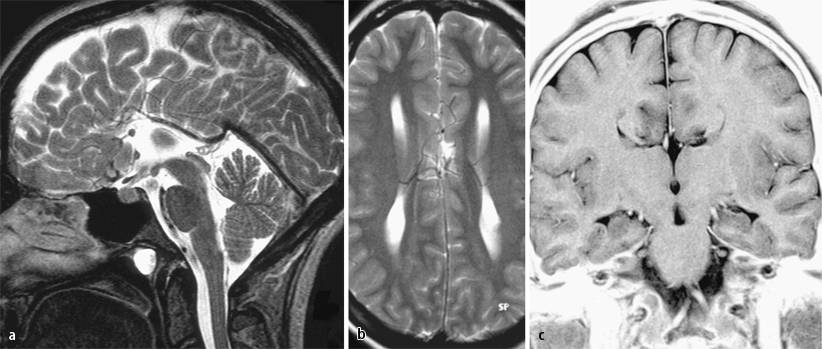

Die Kolpozephalie (von altgriechisch κόλπος kolpos ‚Scheide‘ und altgriechisch κεφαλή kephalie ‚Kopf‘) ist eine abnormale Form des Seitenventrikels mit überproportionaler Erweiterung des Hinterhornes (Cornu posterius/occipitale) bei schmalem Vorderhorn (Cornu anterius/frontale).

Die Diagnose ergibt sich aus der Bildgebung meist zunächst mit Sonographie, ggf. zusätzlich mit Magnetresonanztomographie zur Erfassung von Heterotopien. Sie kann bereits pränatal gestellt werden.